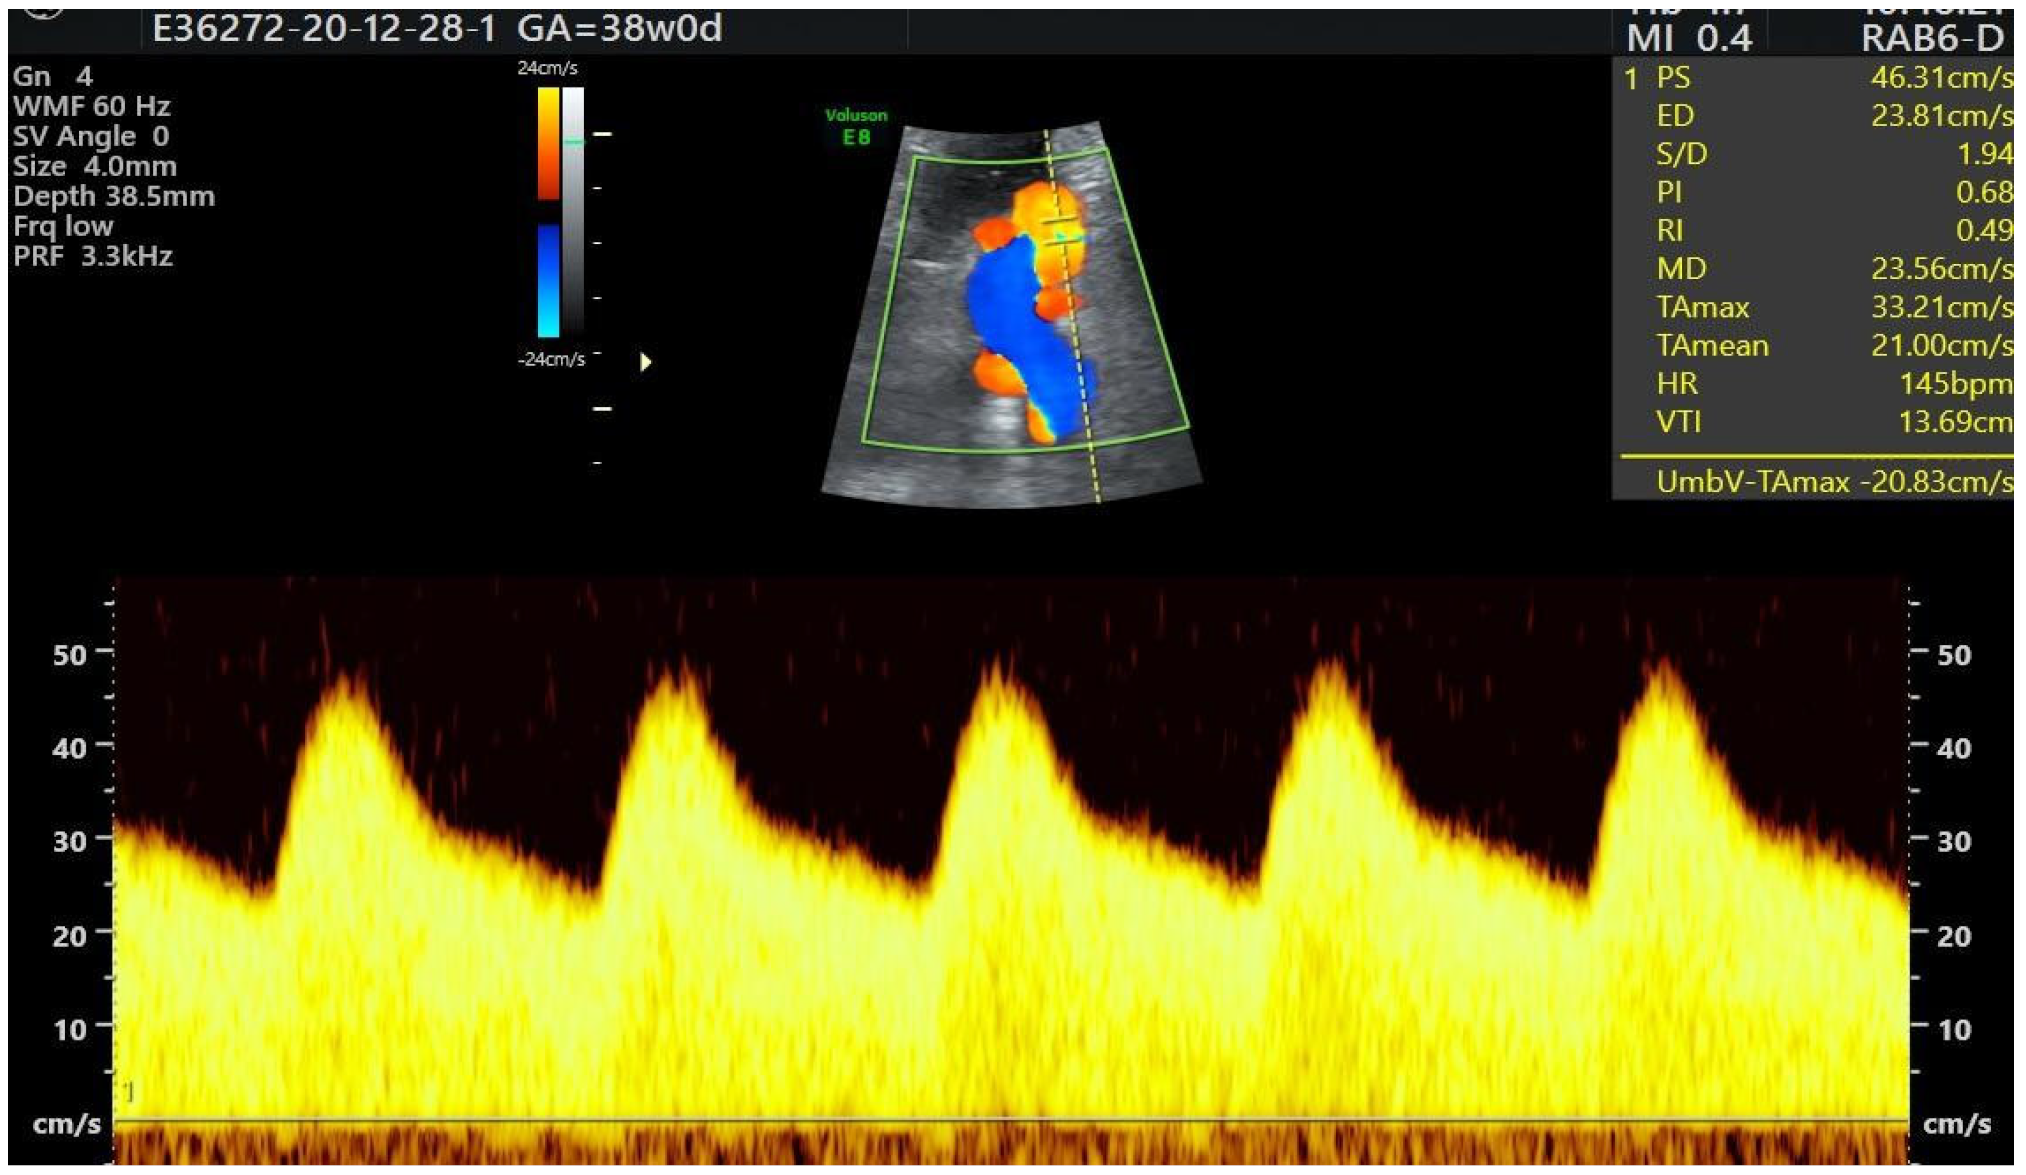

| Color Doppler |

- PS UV;